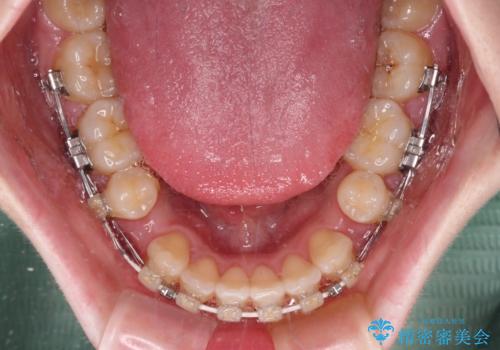

強い舌の突出癖により、上下前歯が前方に飛び出しており、特に上顎前歯は下顎よりも更に前方に位置している状態でした。

上顎前歯をしっかりと後方に移動させるため、口蓋側にアンカースクリューと補助装置を併用し、上下左右の第一小臼歯4本を抜歯し、ワイヤー装置にて矯正治療を行うこととしました。

また、舌のトレーニングをしっかりと行うことで、突出癖改善を試みることとしました。